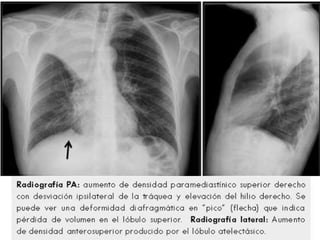

Radiografía de tórax PA: muestra condensación en lóbulo del pulmón

derecho, de limites definidos; y bronco grama aéreo.